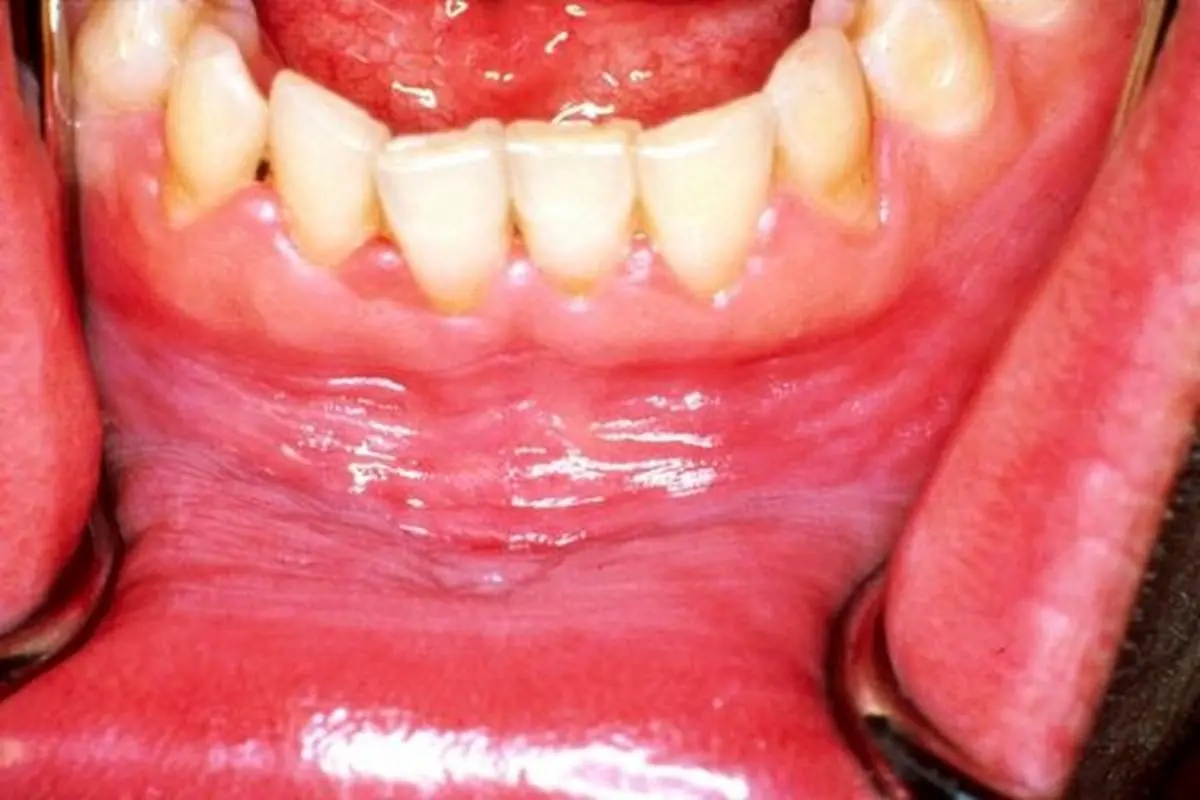

بیماری‌های متعددی می‌توانند موجب سفید شدن لثه‌ها شوند که از آن جمله می‌توان به آفت دهان یا بیماری‌های طولانی مدت التهابی اشاره کرد. همچنین در موارد نادر سفید شدن لثه‌ها می‌تواند نشان دهنده سرطان دهان باشد و به همین دلیل تشخیص مناسب آن حیاتی است.

از جمله بیماری‌هایی که موجب سفید شدن لثه‌ها می‌شود می‌توان به موارد زیر اشاره کرد:

لوکوپلاکی: لوکوپلاکی یک نوع بیماری دهان است که باعث می‌شود بخش‌هایی از لثه سفید شود. بر اثر این بیماری لکه‌های سفید رنگی در دهان ظاهر می‌شود که با مسواک زدن هم برداشته نمی‌شود. بیشتر موارد لوکوپلاکی بی‌خطر هستند اما برخی از آنها می‌توانند پیش زمینه سرطان باشند.

آفت دهان: آفت‌های دهان ضایعه‌هایی داخل دهان و لثه‌ها هستند که می‌توانند دردناک بخصوص هنگام صحبت کردن، غذا خوردن یا نوشیدن مایعات باشد. آفت‌های دهان باعث می‌شود بخش‌هایی از لثه سفید به نظر آیند. هر چند رنگ لثه‌ها در تمامی نقاط دهان سفید نمی‌شود.

لیکن پلان دهانی: بر اثر این بیماری لکه‌های سفید رنگی روی لثه‌ها، زبان و دیگر بافت‌های داخل دهان ظاهر می‌شود. این عارضه یک بیماری خود ایمنی مزمن است که با انواعی از علائم از جمله درد، خونریزی و التهاب لثه همراه است.

افراد مبتلا به این بیماری باید به طور مرتب به دندان پزشک مراجعه کنند چرا که آنان در معرض فزاینده خطر کمبودهای تغذیه‌ای، عفونت دهان و سرطان دهان قرار دارند.

برفک دهان: این بیماری یک نوع عفونت قارچی است که بر اثر آن زخم‌های سفید - کرم رنگ در دهان ظاهر می‌شود. نوزادان، افراد مسن و مبتلایان به دیابت بیشتر در معرض ابتلا به این مشکل هستند.